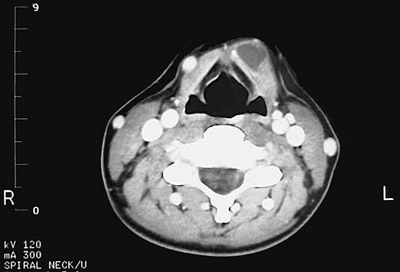

Click on the thyroglossal duct cyst in the CT scan above:

Here is another CT scan in the region of the mid neck at the level of the hyoid bone demonstrating a thyroglossal duct cyst near the midline.